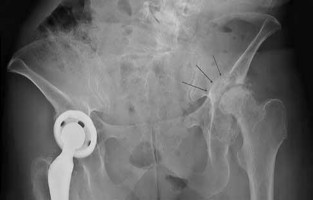

Question 6:

A 72-year-old female undergoes a primary total hip arthroplasty via a posterior approach. Postoperatively, she experiences recurrent posterior dislocations. Radiographic evaluation demonstrates an anteverted cup at 15 degrees and an abduction angle of 40 degrees, with the femoral stem in 5 degrees of retroversion. What is the most likely cause of her instability?

Correct Answer: Femoral component retroversion

Explanation:

Stability in total hip arthroplasty is largely dependent on the combined anteversion of the acetabular and femoral components, which should optimally be between 25 and 35 degrees (Widmer's criteria). In this case, the acetabular cup is anteverted 15 degrees, but the femoral stem is retroverted 5 degrees, resulting in a combined anteversion of only 10 degrees. This relative retroversion significantly increases the risk of posterior dislocation.